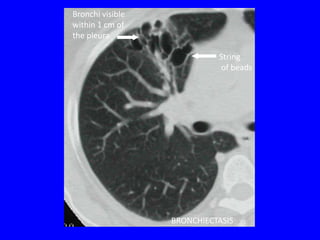

THE CT SCAN

•   Signet ring sign

•   Tram-tracks

•   String of beads

•   Circles filled with air or air and fluid

•   Tubular and branching opacities

•   Bronchi visible within 1 cm of the pleura

BRONCHIECTASIS

Bronchi visible

within 1 cm of

the pleura

String

of beads